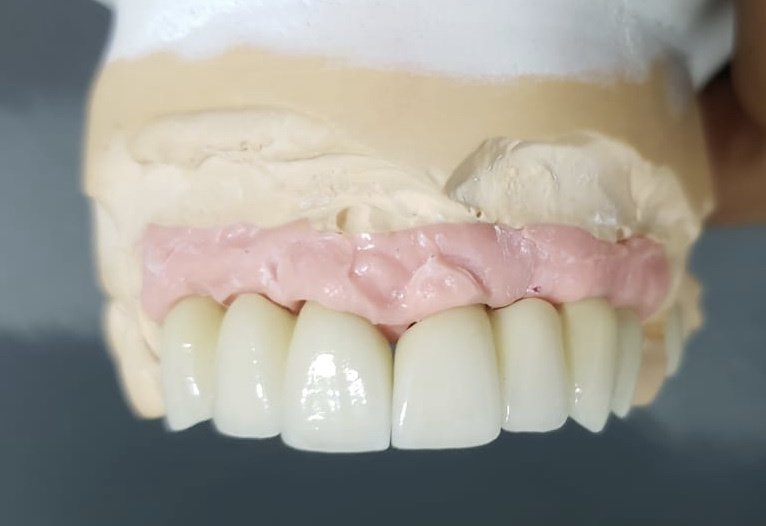

About Live Implants Nicaragua Virgil Mongalo DMD is a dental implant surgeon, past professor of implant surgeries at the University of Miami and the University of Florida has opened a surgical implant center in Managua. This is a state of the art facility consisting of equipped with Ct-scan, 3D Printer, zirconia milling machine, 8 surgical rooms, and USA sterilization controls. His team consists of implant surgeries professor accredited... (Show more)